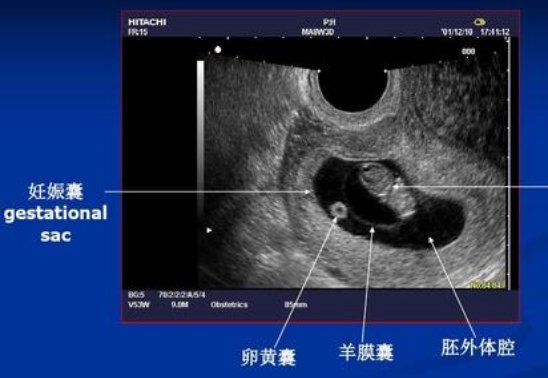

① 第一次B超:刚怀孕,明确孕囊着床的位置

有的医生会在刚怀孕时会给做阴超(因为经腹B超还看不到),目的是为了明确孕囊着床的位置,从而判断是宫内孕还是宫外孕,这是决定是否可以继续妊娠的关键;但也有些医生不建议做,觉得没多大必要。

因此是否在这个时候做B超,主要看医生的安排,若是做的话,这就是第一次B超。

② 第二次B超:孕7周左右,看是否出现胎心胎芽

到了怀孕7周左右,通过B超检查,可以显示宫腔内的孕囊(胎芽)以及原始心管搏动(胎心),而大部分孕妈都会做这个B超。若是刚怀孕时没做B超,那这个B超就算第一次B超。